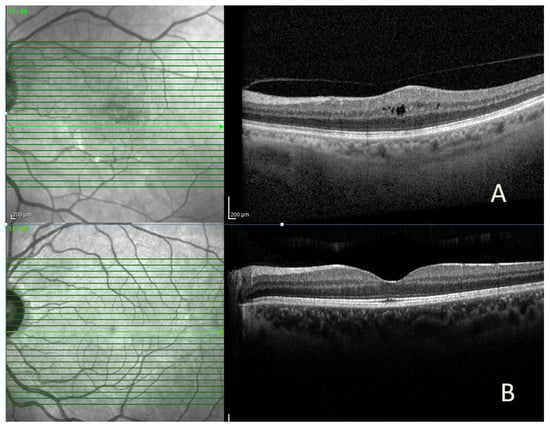

Anatomical success was achieved in 40 (83.3%) of the 48 cases, and complete resolution of ME (dry macula) was achieved in 18 (45%) (Figure 1). In eyes with anatomical success, the median CMT (314.5 vs. 459.6 µ, p = 0.008) and IRT (227.9 vs. 376 µ, p = 0.005) were statistically lower than those without. In contrast, the median GCT, ORT, and CCT were similar (Table 3). In eyes with anatomical success, the median CMT, IRT, GCT, and CCT decreased significantly after treatment compared to baseline, while median ORT did not change. In eyes without anatomical success, quantitative OCT parameters were similar before and after treatment (Table 3).

Figure 1.

Representative spectral-domain optical coherence tomography (SD-OCT) images of a patient with diabetic macular edema, showing (A) intraretinal cyst and increased central macular thickness before intravitreal bevacizumab injection and (B) marked reduction in macular edema after treatment.